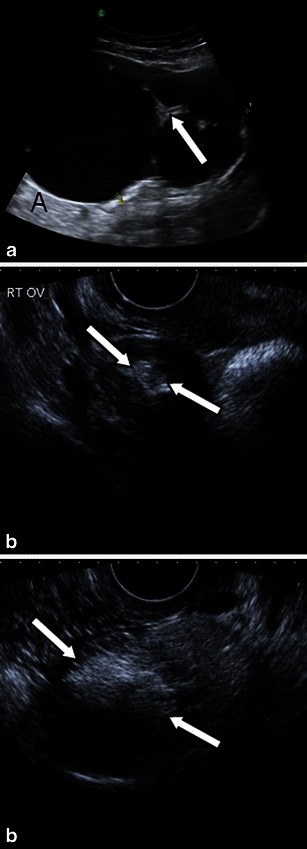

Ultrasound

Whilst a mature teratoma or dermoid cyst presents on ultrasound as a cystic lesion with a densely echogenic tubercle (termed a Rokitansky nodule or nidus), which projects into the cystic lumen [3], as well as associated sound attenuation due to sebaceous material and hair within the cyst cavity or recognisable fluid–fluid levels from the sebum floating above aqueous material [3, 23], the ultrasound features of a struma ovarii are quite indistinct (Fig. 3). As struma ovarii presents with a variety of non-specific appearances and usually manifests as a multilocular cystic ovarian mass with solid components of various amounts, the ultrasound typically demonstrates these non-specific heterogeneous solid cystic features [3].

Fig. 3.

Difference in ultrasound features between struma ovarii and ovarian dermoid cyst. a Predominantly cystic struma ovarii typically mimicking an epithelial ovarian tumour (either cystadenoma or borderline ovarian tumour) in the right ovary of a 51-year-old patient presenting with non-specific abdominal cramps. Some thicker septations are seen (arrow) between otherwise cystic areas presenting with anechoic fluid and posterior acoustic enhancement (A).Right 1.5-cm (b) and left (c) 5.1-cm dermoid cyst in a 24-year-old woman. Both lesions on ultrasound have the typical pattern of high attenuation within the cyst (arrows) representing its fatty component